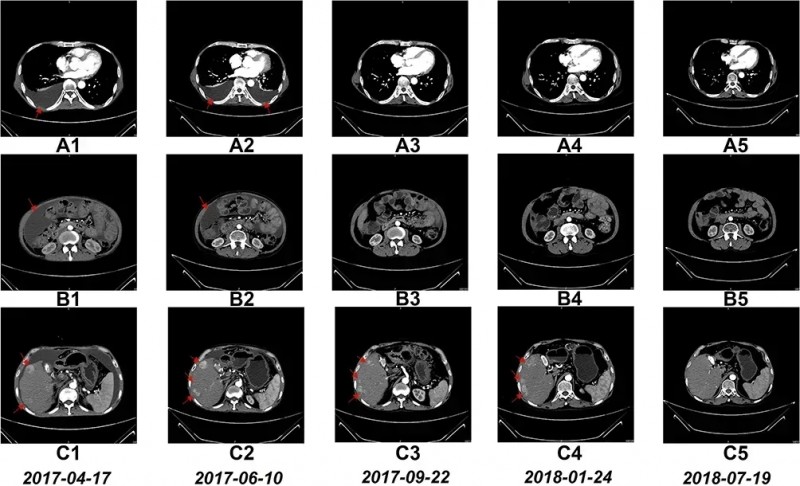

全球著名期刊《Oncotargets and Therapy(肿瘤靶点和治疗)》曾报道一例NK细胞治疗晚期肝细胞癌的案例,该患者经治疗后生存时间已超过4年。这名患者为59岁男性,既往患有慢性乙肝,确诊时为晚期弥漫性肝细胞癌(HCC,TNMIV期)。他此前接受过腹膜穿刺手术、顺铂化疗、经导管动脉化疗栓塞术(TACE)等治疗,但效果均不理想,随后入组接受NK细胞回输治疗,共完成17个疗程。

结果显示:治疗6个疗程后,复查CT显示患者胸水完全消失、腹水几乎完全消失。治疗17个疗程后,复查CT可见其肝右叶多个肿瘤病灶均显著缩小。具体表现为:治疗6个疗程后胸腔积液消失(详见下图A1~A5);治疗6个疗程后腹水几乎消失(详见下图B1~B5);治疗17个疗程后肝右叶肿瘤缩小(详见下图C1~C5)。

此外,该患者在接受NK细胞回输16个月后,甲胎蛋白(AFP)显著下降,预示病情逐渐稳定、癌症进展得到控制、肿瘤负荷明显减轻(详见下表)。根据EORTCQLQ-C30(癌症患者生活质量评分量表)评估,患者治疗后的生活质量明显提高:症状维度得分从治疗前的60降至≤10,健康维度及功能维度得分则从治疗前的≤20升至80左右。目前,该患者已存活超过4年。